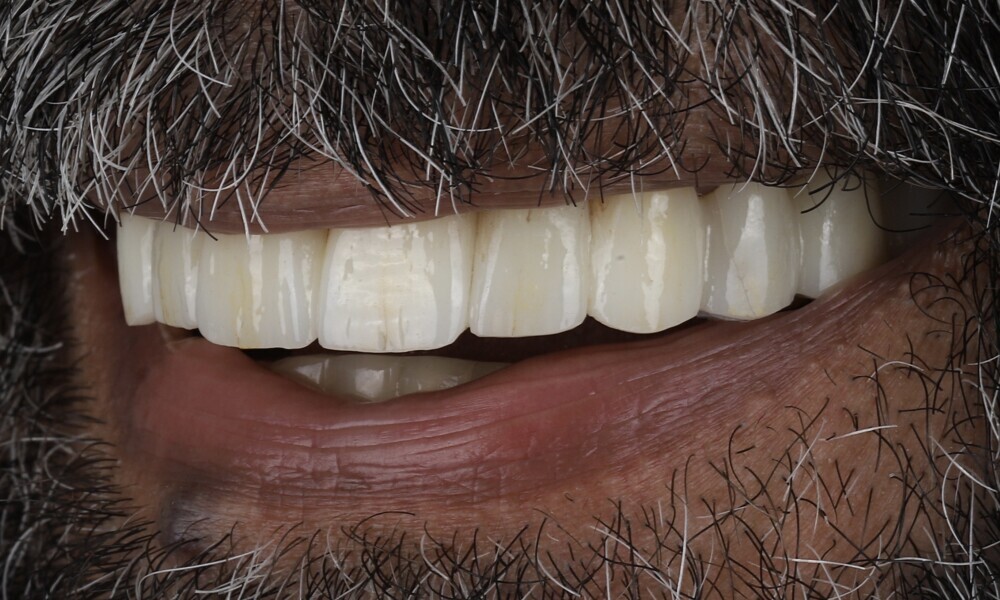

The delivery of the final prosthesis was then performed, and the aesthetics, occlusion and function were verified (Figs. 51–55). The panoramic control radiograph showed that all measurements were within expected ranges (Fig. 56).

At the 18-month follow-up after completing the treatment, an intra-oral, extra-oral and radiographic evaluation were performed. No pathologies were observed, and the results remained stable over time (Figs. 57–62). The patient expressed his satisfaction with the treatment outcomes, stating, “Seeing my new smile before starting the procedure was a game-changer. I was confident from the beginning that my final result would be as I had imagined.”